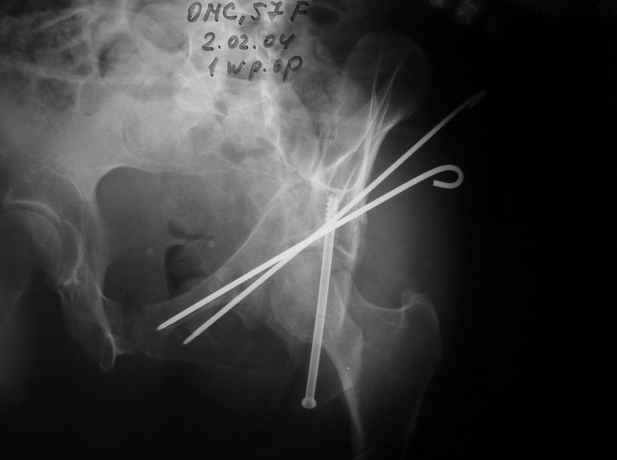

Однако есть альтернатива. Репозиция из подвздошного доступа тазовыми щипцами с разнодлинными браншами или тазовым пистолетом, а фиксация задней колонны через седалищный бугор или тазрвыми винтами 4,5 или каннюлированными 6,5 или 7,3. По-моему я посылал на ортофорум такой снимок, когда жаловался на ишемический неврит седалищного нерва через сутки после операции. Не забудь про шейку бедра - мне кажется будет хорош длинный PFN любой фирмы, какую ты найдешь, а нет так UFN + miss a nail, как это здорово делают мои земляки - Ебурбуки. Пока.

02.02.04

Откровенно говоря, репозиция оказалась очень непростым делом, несмотря на то, что при расширенном илео-феморальном доступе все переломы как на картинке.

Сначала пытался отрепонировать смещенную заднюю колонну, но ничего из этого не получалось пока не репонировал фрагмент крыла подвздошной кости, который клином входил между отломками тела илии и задней колонной дистанция-то всего каких-то 3-5 мм, но чтобы сложить этот puzzle пришлось попотеть, я уже и дистракционные щипцы и бедренный дистрактор крутил, в конце концов все состоялось, а передняя колонна уже саморепонировалась, мне оставалось только компрессирующие винты завинтить

Приблизительно так и сделал